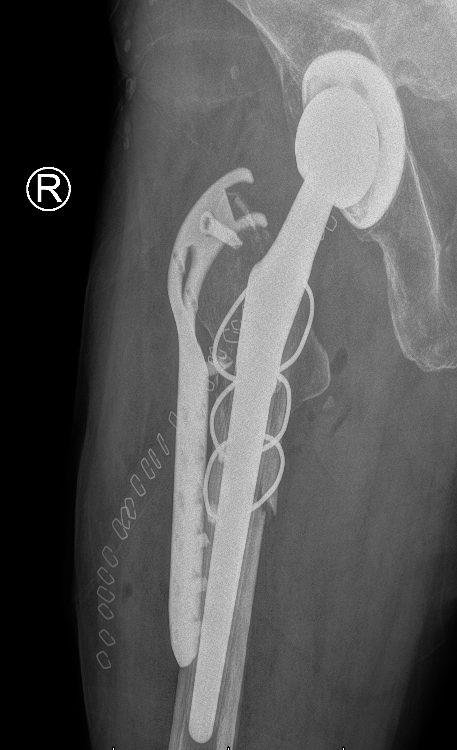

王女士二次受伤后影像检查提示假体周围骨折